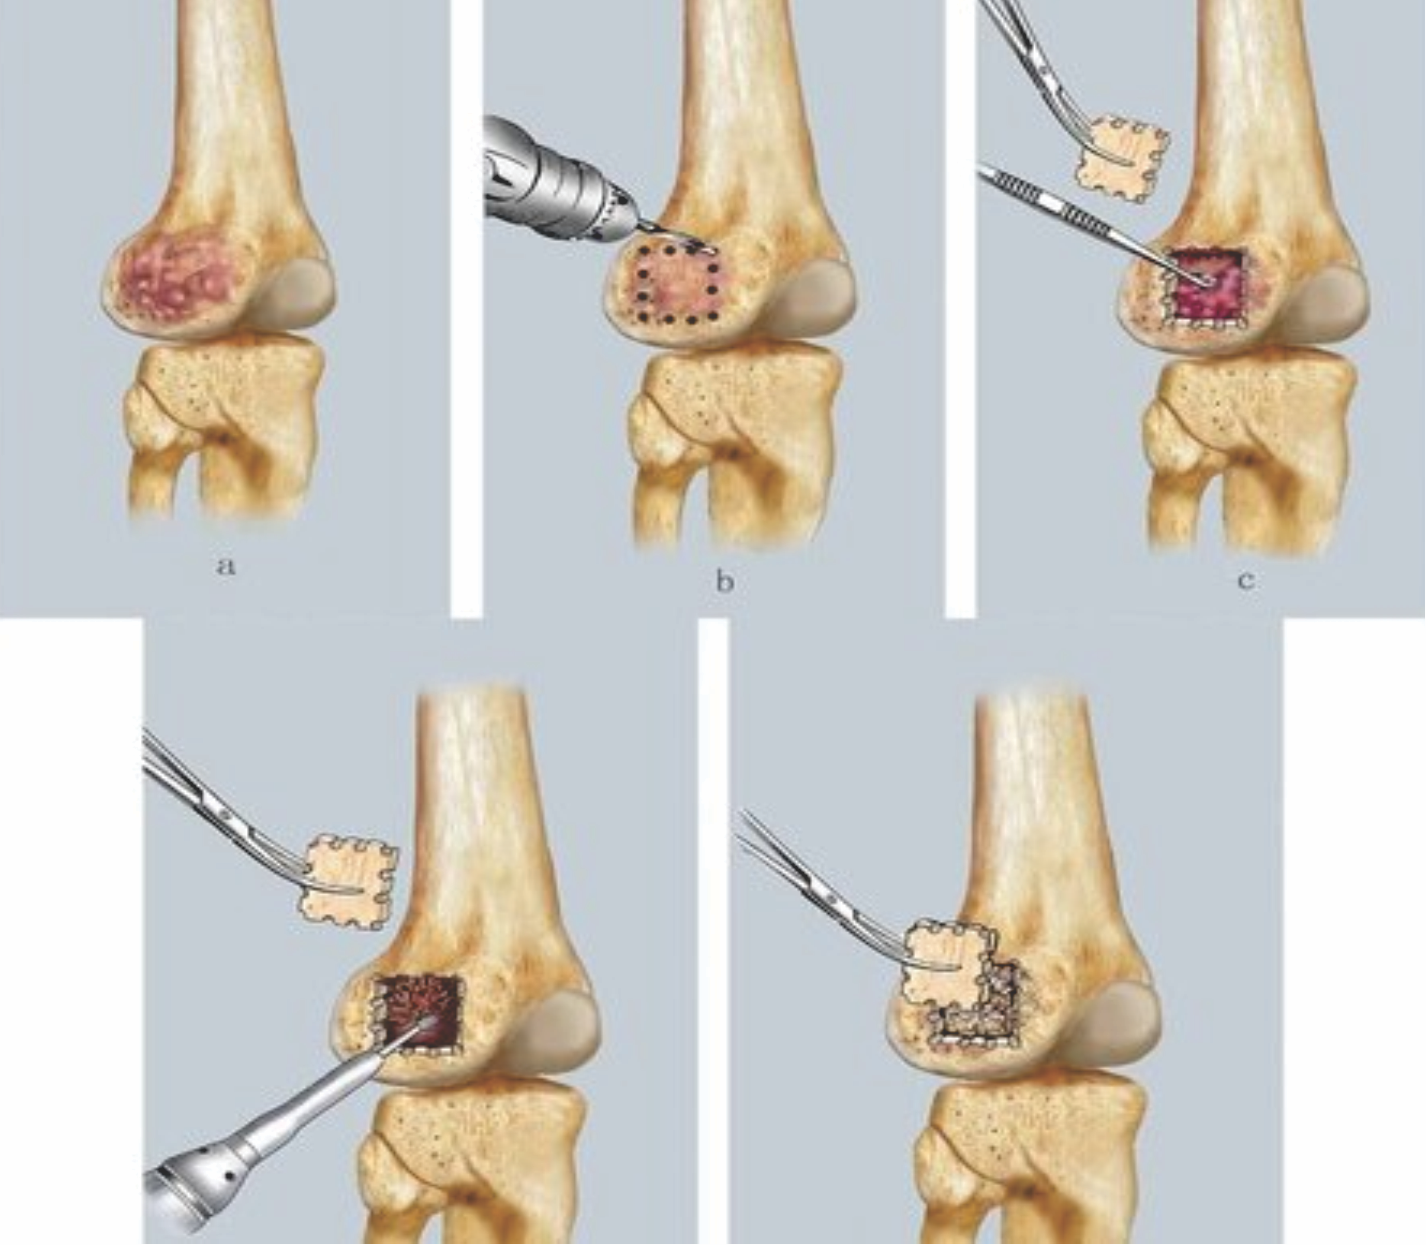

Various surgical techniques followed for GCT have been local procedures, such as wide resection, marginal resection (Fig. 3 and 4), and radical procedures, such as ray amputation, disarticulation (Fig. 4) [3].

Figure 3: Bone currettage followed by cementing or bone grafting has been the most commonly practiced technique for giant cell tumor.

Of all surgical techniques, bone curettage followed by cementing or bone grafting has been the most commonly practiced technique for GCT (Fig. 3). This technique involves raising a cortical osseous flap of affected bone. Then extended curettage of the lesion is done with a high-speed burr device, and phenol is used as an adjuvant. Electrocautery is used at margins for neutralizing marginal tumor cells. Finally, the lesion is filled with polymethyl methacrylate cement or bone graft. Ultimately, the defect was closed with the same osseous flap.

Figure 4: Local procedures like wide resection, marginal resection. Radical procedures like ray amputation, disarticulation.